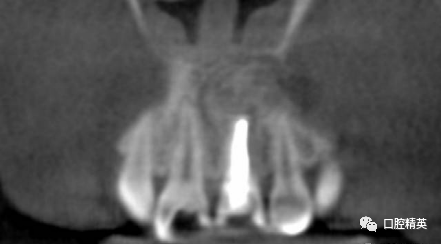

CBCT检查发现21内吸收,已做根充。根尖周可见约10mm*7mm*7mm范围低密度影像,近11,22根尖区。边界清楚。可见超充药物,查看病历曾使用碘仿和VITAPEX。

考虑21慢性根尖囊肿。拟定行囊肿切除+根尖切除倒充术。详细交代可能出现并发症,病人理解同意手术治疗。延期进行牙齿美白和美容性修复。完善术前检查,择期手术。